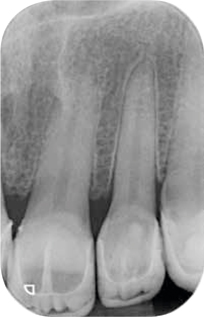

Afb. 11-12

Bitewings. Met de initiële fase is al een aanvang gemaakt.

Röntgenonderzoek

Röntgenologisch onderzoek laat meerdere problemen zien. Onder andere een forse zwarting apicaal van element 12 met het beeld passend bij periapicale problematiek en een verleden van apicale chirurgie (afbeelding 8-12 ).